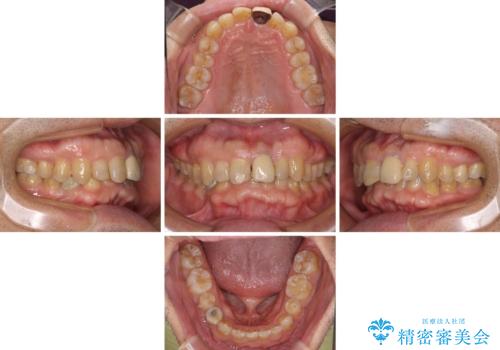

- 上下前歯のデコボコと下顎小臼歯の欠損によるスペースを気にして来院された患者様です。

下顎は左右1本ずつ小臼歯が欠損しており、右側にはやや大きな欠損がありました。

欠損により下顎歯列は相対的に小さく、上顎に深く咬みこんでしまうディープバイトとなっていました。

インビザラインによる治療を希望されたため、左側のスペースは閉じ、右側はスペースをより拡大し、インプラント補綴を行うこととしました。

咬合力が強く、インビザラインのみではディープバイトを改善することができず、半年間ほどワイヤー装置による矯正治療を行いました。

インプラントの埋入は矯正治療中に行い、矯正治療後はインプラント上補綴および、前歯のセラミック治療を行いました。